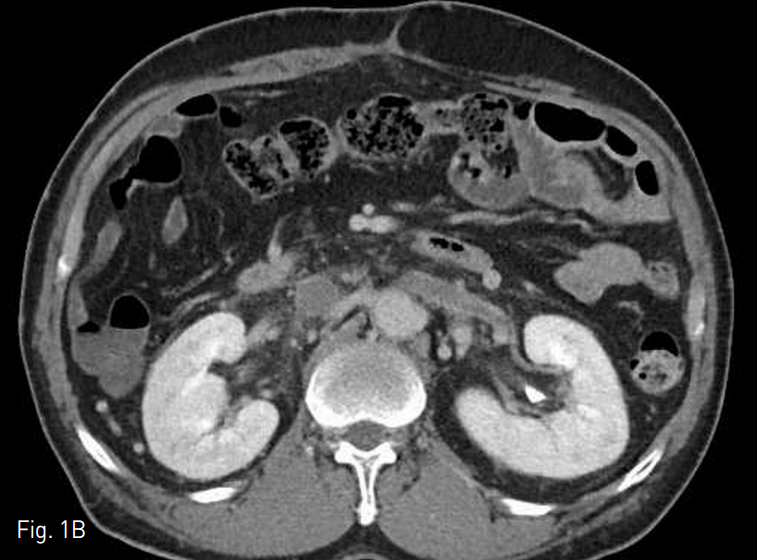

초음파 유도하에 오른쪽 총대퇴정맥을 천자하였고, 5 Fr cobra catheter (Cook, Bloomington, IN, USA)를 삽입하여 정맥조영술을 시행한 결과 혈전으로 폐색되어 있는 간하부 하대정맥과 양측 신정맥 내부의 혈전 및 다수의 측부 순환들이 관찰되었다 (Fig. 2). 왼쪽 총대퇴정맥에 11 Fr arrow long sheath (Johnson & Johnson Medical, New Brunswic, Canada)를 삽입하여 왼쪽 장골 정맥과 하대정맥 내에 있던 혈전을 흡인하였고, 6 Fr fogarty balloon catheter (Edward Lifesciences, Irvine, CA, USA)을 이용하여 왼쪽 장골 정맥에 유착되어 있던 혈전도 제거하였다 (Fig. 3). 왼쪽 장골 정맥과 하대정맥 내에 잔재하는 혈전에 대해서는 MCIS thrombolysis catheter (Cook, Bloomington, IN, USA)를 삽입하여 밤 사이 12시간 동안 시간당 80,000 unit의 속도로 urokinase를 투여해서 혈전 용해술을 시행하였으며, 동시에 양측 총대퇴정맥 sheath를 통하여 heparin을 시간당 150 unit을 각각 투여하였다. 간내부 하대정맥의 혈전으로 인해 하대정맥 필터 삽입술은 시행하지 않았다.

Fig. 3

A. Left iliac vein thrombus was removed using 6 Fr fogarty balloon catheter.

B. Aspiration thrombectomy was also done in left iliac vein.